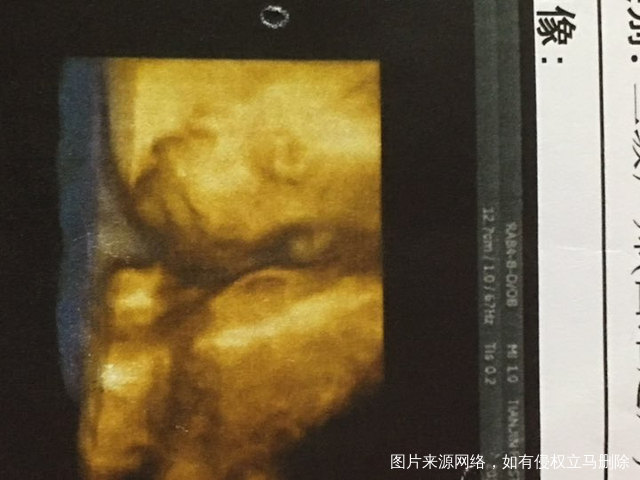

今天做四维了,第一次看见宝宝的照片很激动……激动的落泪,记得当初做试管道路上的艰辛一切都值得的,宝宝长的很可爱,希望宝宝眼睛大大的[偷笑]